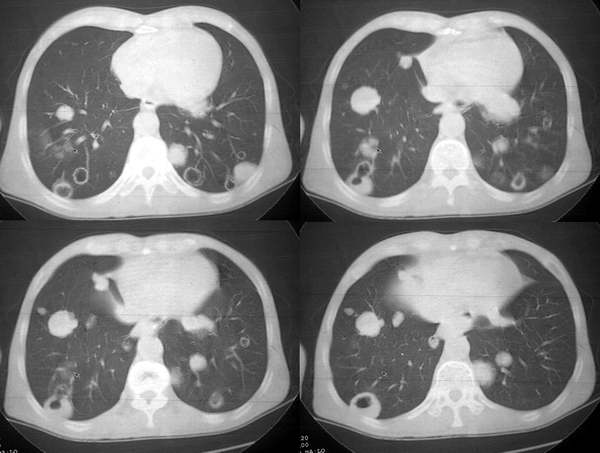

男62肺癌治疗后复查

具体治疗措施不清楚,治疗前空洞很少,请讨论空洞的性质

双肺内及胸壁旁见有多发软组织实性阴影和空洞,实性病变多见有脐凹切迹,贴近胸膜的见有胸膜凹陷征;空洞的壁多为厚薄不均,形态不规则,纵隔内见有较多肿大淋巴结,诊断为双肺内转移性病变。

双肺内及胸壁旁见有多发软组织实性阴影和空洞,实性病变多见有脐凹切迹,贴近胸膜的见有胸膜凹陷征;空洞的壁多为厚薄不均,形态不规则,纵隔内见有较多肿大淋巴结,诊断为双肺内转移性病变。[气囊或孔洞实为腺癌缘肺泡壁生长所致]

肺癌双肺内多发空洞转移,原发灶多为腺癌,恶性程度较高.

考虑肺癌肺内空洞性转移(cpm)。

cpm灶多为圆形或类圆形、无分叶和毛刺,说明除空洞外cpm 基本保留了转移瘤的形态特点。本组中单个病例出现cpm灶1 16枚,多发与单发者大致相等,说明cpm瘤灶的数目变化大。全部病例的cpm灶均是与肺内多发实性瘤灶共存,而且后者往往远多于前者。另外,当病情好转或恶化时,cpm灶与实性瘤灶同时缩小或增大,说明两者呈同步变化。笔者认为这两点是cpm 最恒定的ct特点。•

单个cpm灶的空洞形态具有多样性,壁可薄可厚,厚度可均匀可不均匀,瘤灶大小变化也大。但总的说来,cpm 的洞壁较薄,4mm以下者最多(53%),其次为4—15mm者(34%),而15mm以上者却较少。另外洞壁厚度均匀者也较多(47%)。笔者认为这些与壁薄而均匀的囊样及小环形空洞较多有关。一般认为壁薄而均匀者多为良性空洞,而癌性空洞的壁多较厚或厚薄不均。woodring等-8 j认为洞壁厚度4mm以下者92%为良性,15mm 以上者95%为恶性,15mm者良恶性各半。蒋瑾等-9 j发现83% 的原发空洞型肺癌的壁厚度超过15mm。以上说明cpm的空洞形态不同于肺良性空洞及原发癌性空洞,具有其独特性。本组40%(16/40)的病例中同时存在多种空洞,说明cpm病例具有空洞类型的混合性。同样的洞腔变化既可见于病情好转时,也可见于病情恶化时,特别是同一种病例可同时出现两种相反的洞腔变化,说明洞腔变化具有非恒定性。

右肺门软组织块影,右主支气管及中间段支气管管壁明显增厚,两肺内多发结节及大小不等的类圆形薄壁空洞,纵隔内多发肿大的淋巴结;

考虑:1.右中央型肺癌伴两肺广泛性转移及纵隔转移。

2.多发性空洞需和霉菌性空洞鉴别。